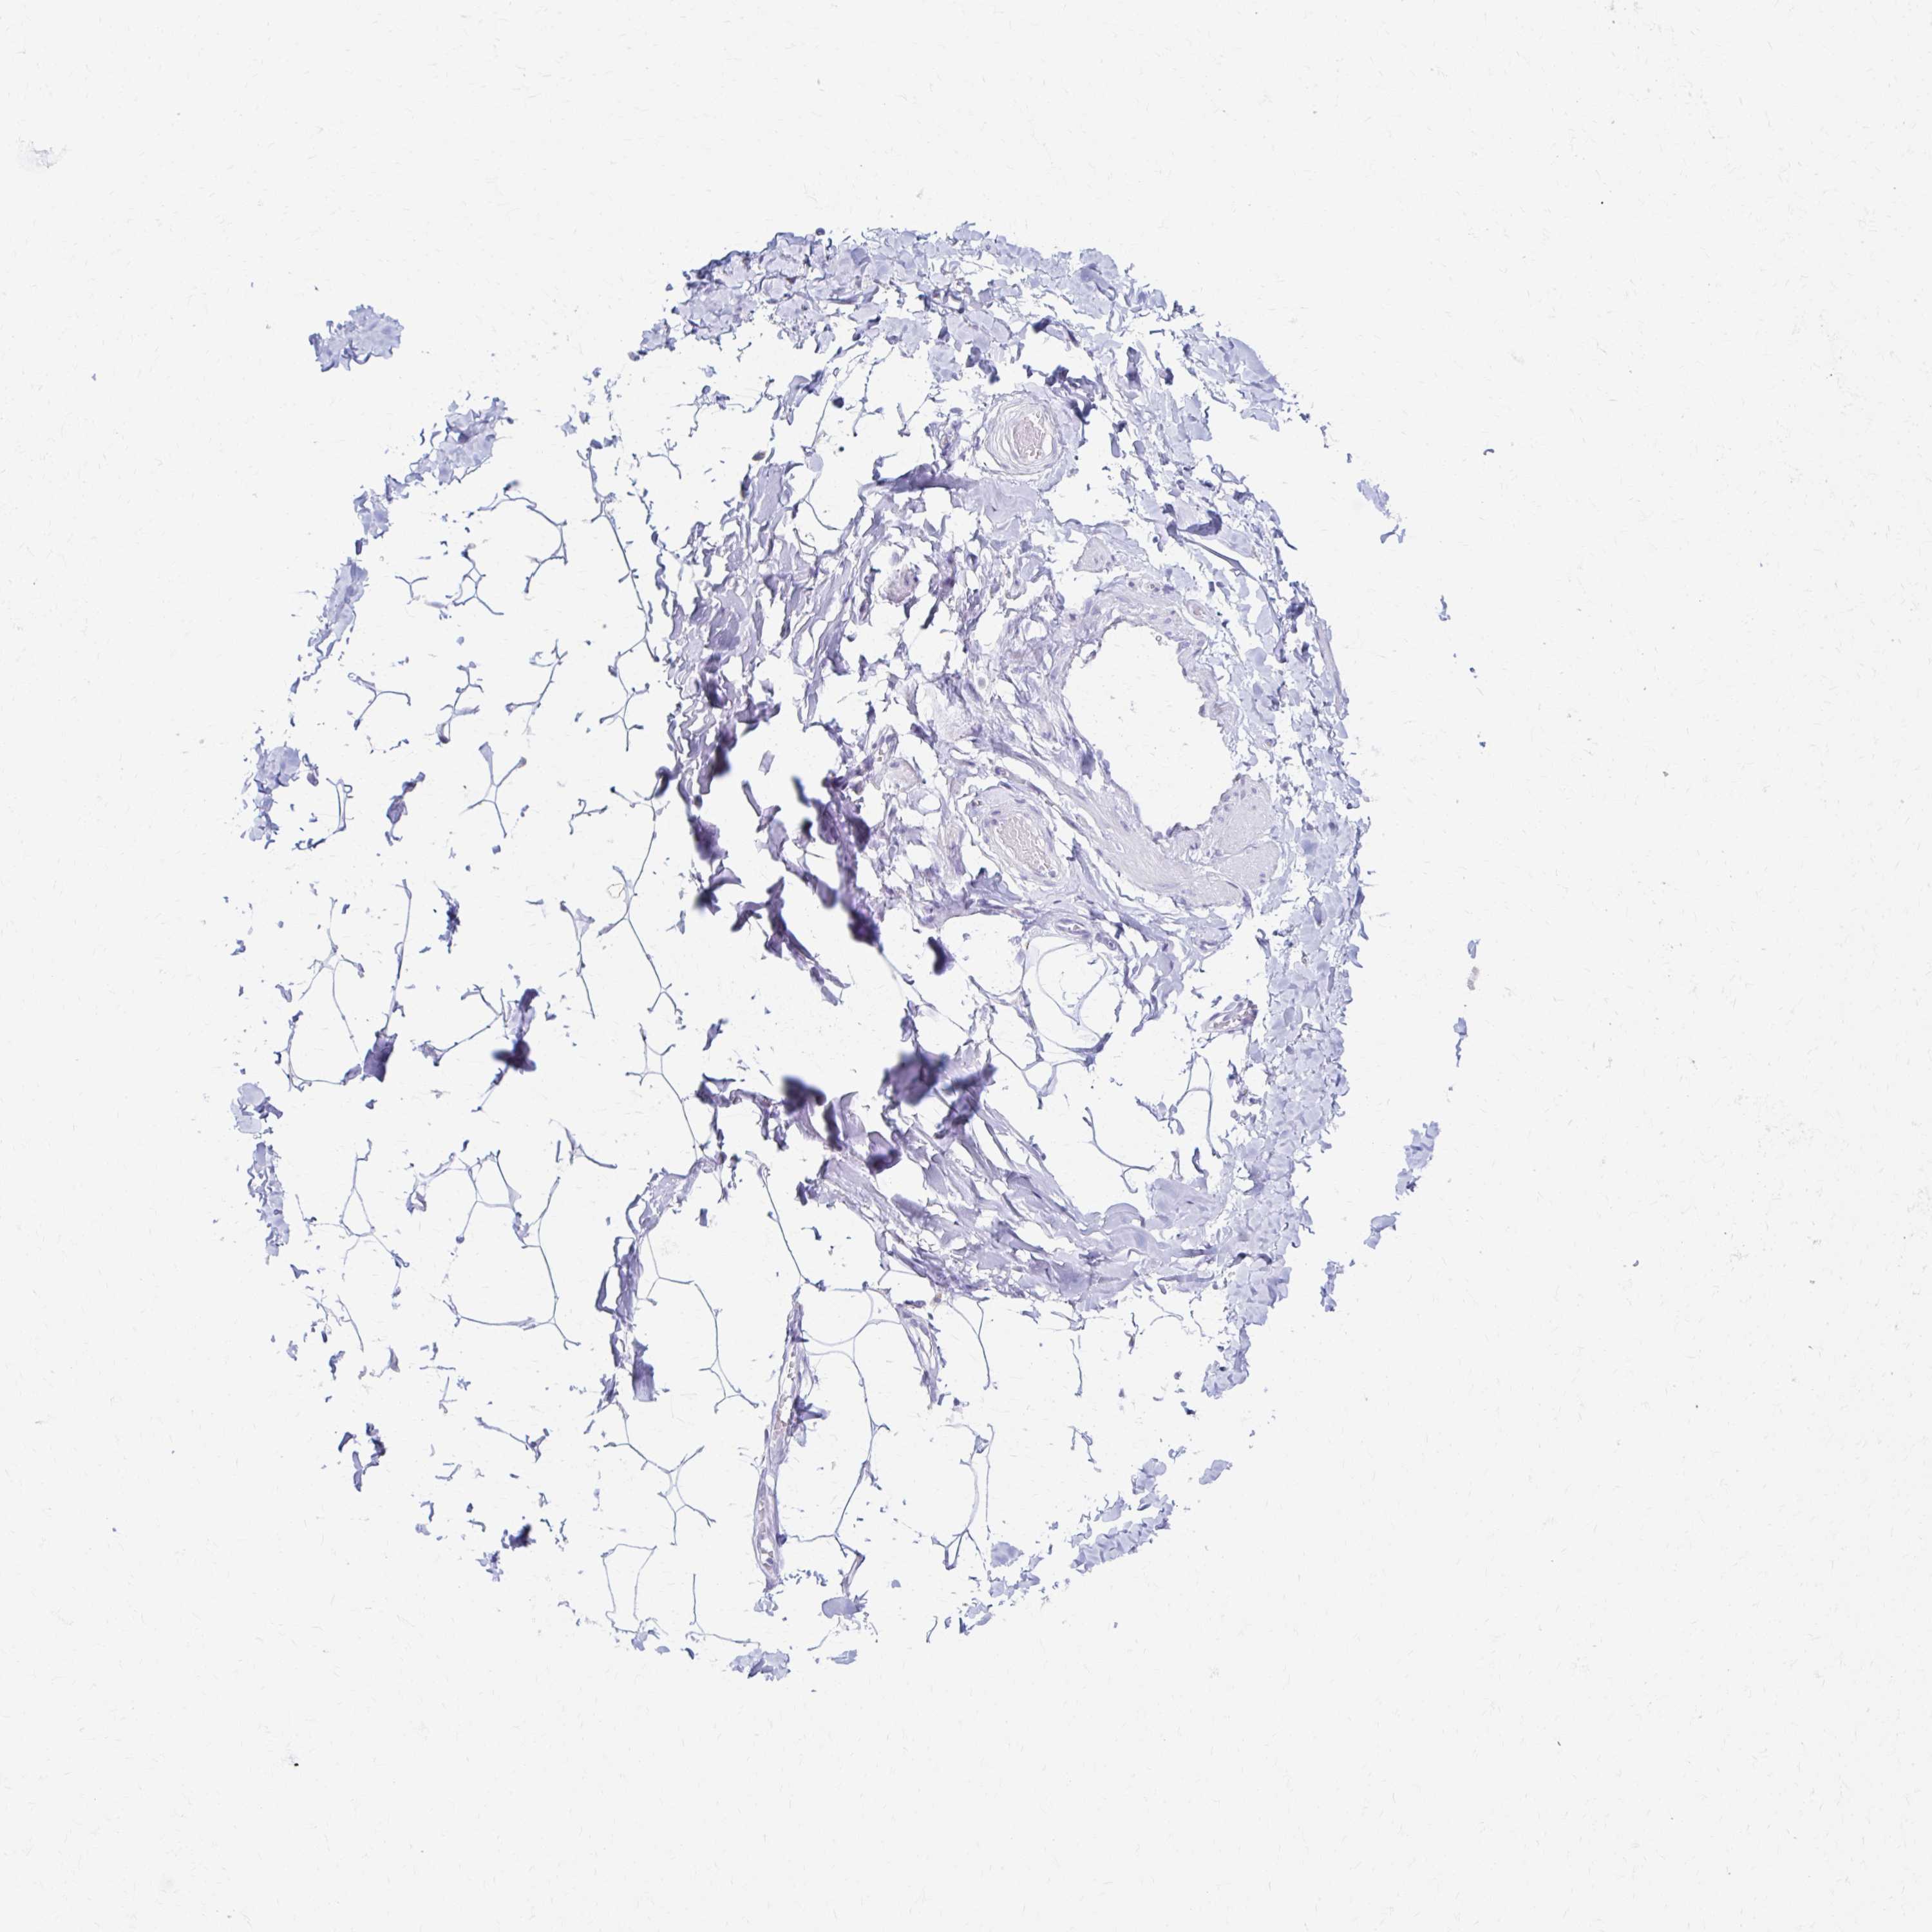

PRKCG